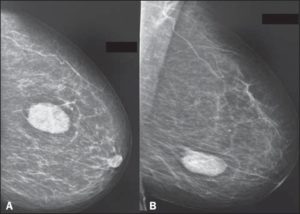

- Диагностическая маммография. Маммография использует рентгеновское излучение для получения изображения (маммограммы) подозрительных участков ткани молочной железы. Если маммография показывает, что присутствует опухоль в груди или другая аномалия, для дальнейшей оценки опухоли назначается биопсия..

- Маммография. На маммографии видна не только сама фиброаденома, но и сопутствующий ей явления – например, кальциноз.